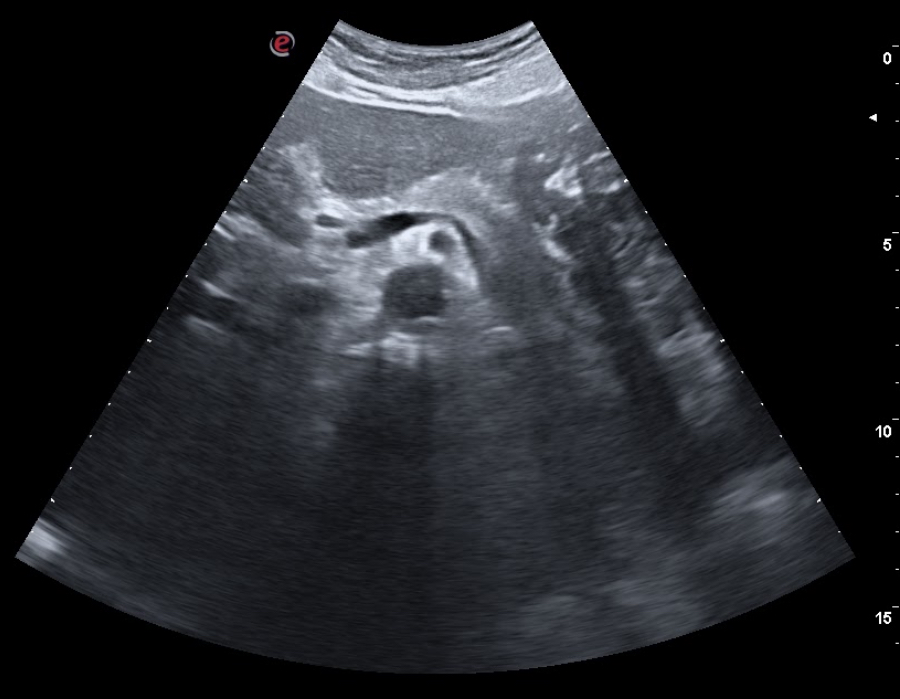

En consulta decidimos realizar ecografía clínica abdominal mostrando hígado de ecoestructura y tamaño adecuados, con vena porta y suprahepáticas permeables, con vesícula biliar repleccionada sin ecos en su interior, páncreas visible sin alteraciones, riñones con buena diferenciación córtico-medular con vejiga reflexionada sin ecos en su interior, útero involucionado, y una masa dependiente de fosa ilíaca derecha de 5×5 cm de ecoestructura similar a un riñón, correspondiente al área explorada.